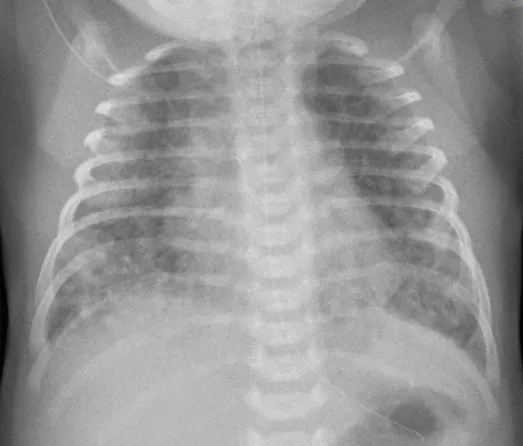

임신 나이 42주 2일, 4200g으로 태어난 아이가 출생 5일 후 갑작스럽게 호흡곤란을 보였다. 태어날 당시 양수는 태변으로 오염되어 있었다. 고농도 산소를 제공하였으나 호흡곤란은 개선되지 않았고, 오른쪽 손의 산소포화도는 85%였으나, 왼쪽 발의 산소포화도는 이보다 12%나 낮았다. 심초음파에서 동맥관이 열려있었으며 우좌 단락이 관찰되었다. 가슴 X선 사진을 찍었다. 치료로 적절한 것은 무엇인가?

• 태어날 때 태변 착색이 있었던 점, 현재 가슴 X선 사진 상 불규칙한 폐음영 감소 소견으로 보아 MAS를 의심할 수 있다. 이로 인해 폐혈관 저항이 감소하지 않아 동맥관이 열려 있게 되며, 우좌단락이 관찰된 것으로 볼 수 있다. 오른쪽 손, 왼쪽 발의 산소포화도 차이 또한 동맥관 전 후로 우좌단락이 발생하여 산소포화도가 감소하기 때문이다.